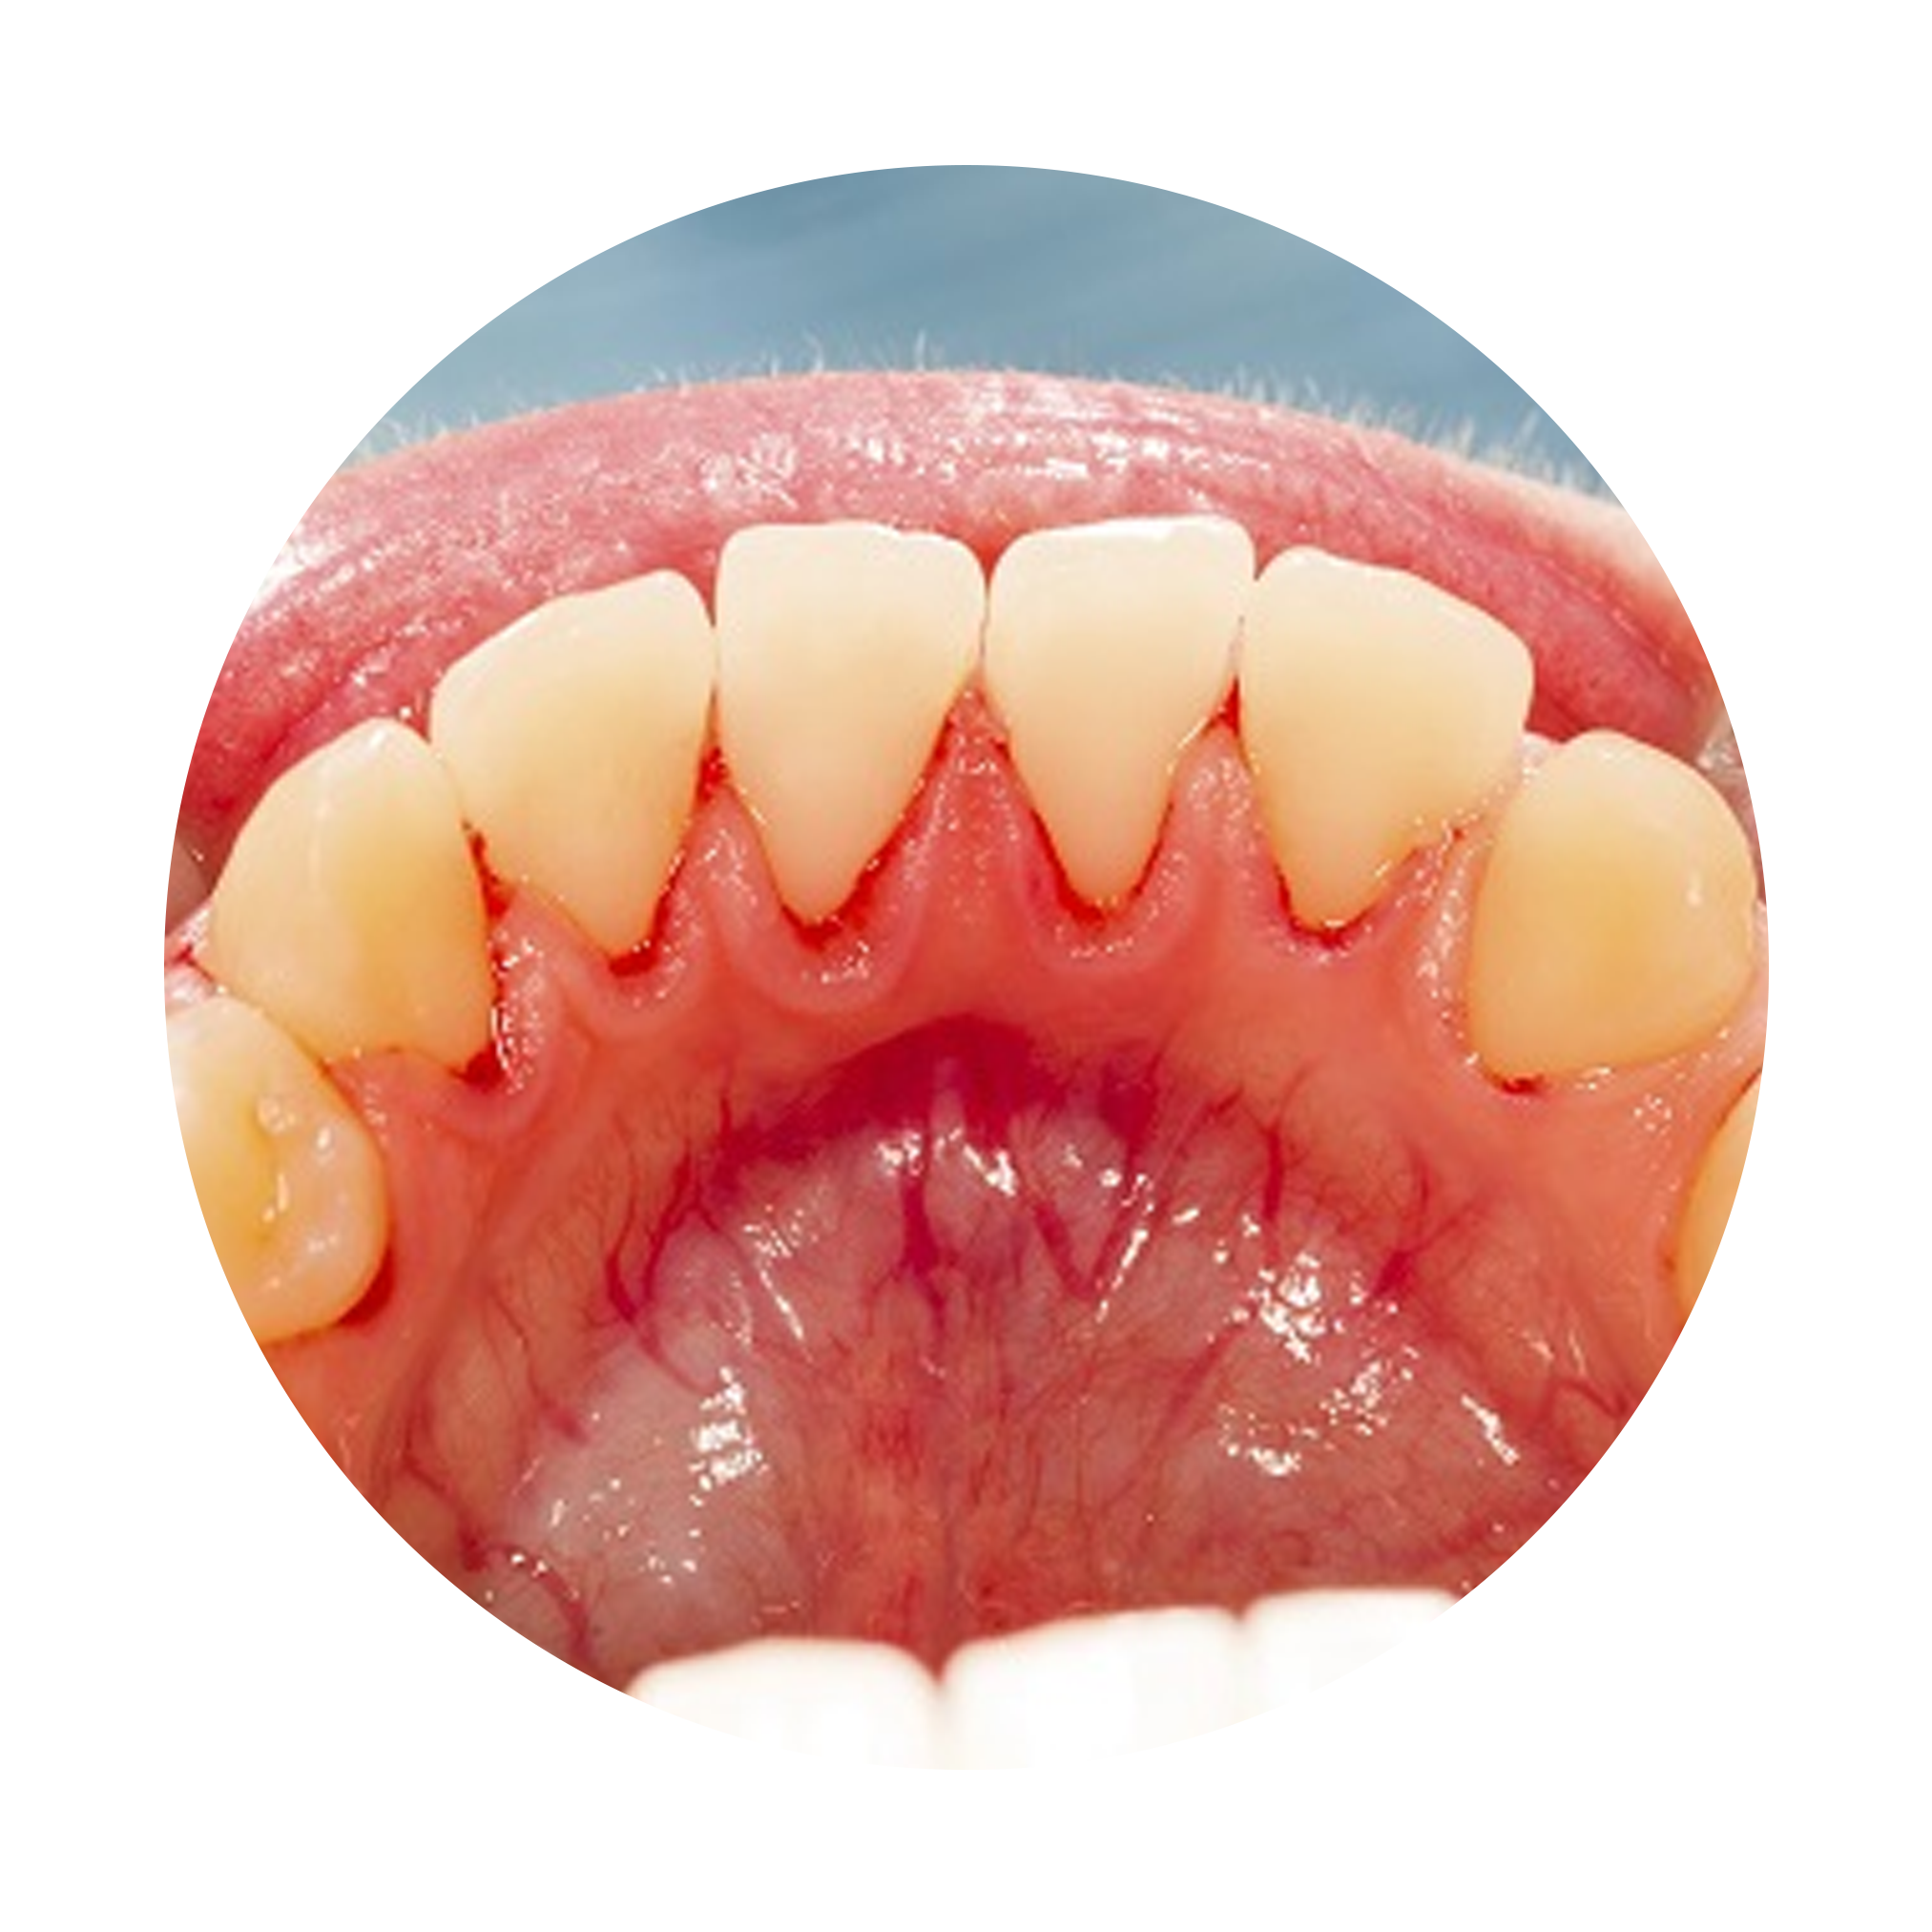

Addressing gum recession early can help save your smile and avoid further complications. Gum recession is a common dental condition where the gum tissue surrounding the teeth wears away or recedes, exposing the tooth roots.

This not only affects the aesthetics of your smile but also poses potential oral health risks. If left untreated, gum recession can lead to tooth sensitivity, increased risk of dental decay, root surface exposure, and even tooth loss.